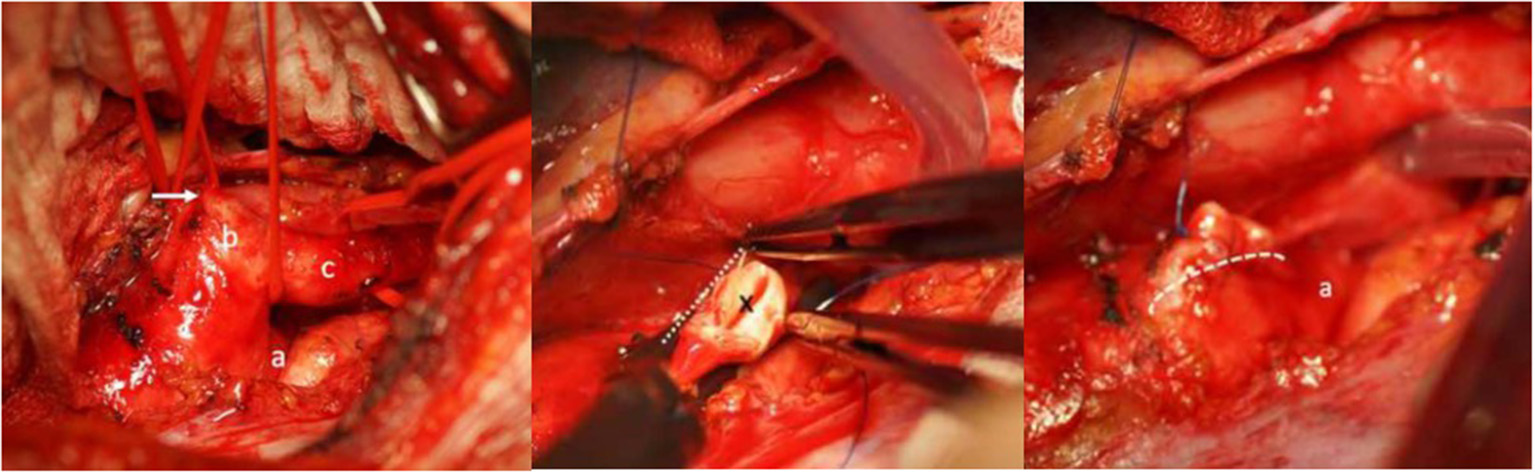

A 31-year old woman with a history of bronchial asthma during adolescence was referred because of worsening shortness of breath during minimal exercises at work. A CT-scan was performed and surprisingly showed a right descending aortic arch with an abnormal left subclavian artery (lusorian artery) taking-off from a rather large Kommerell diverticulum that led to a significant compression of the trachea (Figure 4). A bronchoscopy confirmed this observation with a pulsating mass and a “slit-like” narrowing of the trachea. Surgical approach was performed through a left lateral thoracotomy. The ductus ligamentum was divided, and the left subclavian artery was detached from the Kommerell diverticulum and re-implanted more distally into the descending aorta. Finally, the distal aortic arch was clamped tangentially and the Kommerell diverticulum was resected (Figure 5). The intraoperative bronchoscopy at the end of the operation showed a broad opening of the trachea. Postoperative CT-scan did not show any residual tracheal compression (Figure 6).

Figure 4

Right descending aortic arch with left arteria lusoria originating from a Kommerell diverticulum (*) with compression of the trachea. Reproduced with permission from Cardiovasc Med: w10132: doi 104414.

Figure 5

Left: Intraoperative view showing the distal aortic arch (a), the large Kommerell diverticulum (b) and the left subclavian (lusorian) artery (c). The white arrow shows the ductus ligament. Middle: The abnormal left subclavian artery has been transected from the Kommerell diverticulum at its origin (*), the aortic arch is clamped tangentially and the Kommerell diverticulum resected. Right: Picture after resection of the Kommerell diverticulum and longitudinal suture (dotted line) of the aortic arch. A) represents the aortic arch coming from posteriorly. Reproduced with permission from Cardiovasc Med: w10132: doi 104414.

Figure 6

Postoperative CT-angiography after resection of the diverticulum (dotted line). Just on the right is the distally translocated left subclavian artery. Reproduced with permission from Cardiovasc Med: w10132: doi 104414.

The patient was controlled 6 months postoperatively and was completely asymptomatic with considerable improvement of the physical performance.